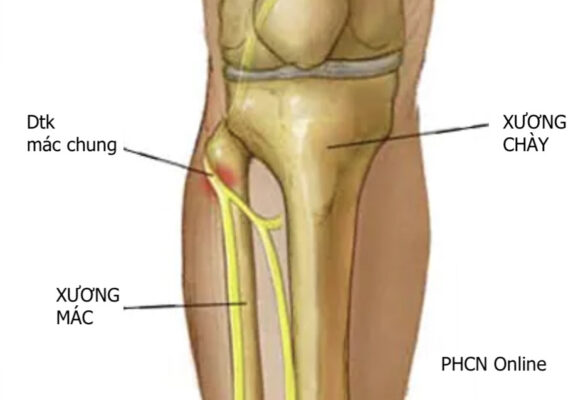

Dây thần kinh mác chung là một dây thần kinh lớn chi phối cho chi dưới. Nó là một trong hai nhánh chính của dây thần kinh tọa (nhánh kia là thần kinh chày) và nhận các sợi từ các ngành sau của các rễ thần kinh từ L4 đến S2. Dây thần kinh mác chung tách dây thần kinh chày ở phía dưới mặt sau đùi gần hố khoeo. Sau khi tách khỏi dây thần kinh chày, nó tiếp tục chạy xuống đùi, chạy phía sau dưới đến cơ nhị đầu đùi (phân nhánh vận động cho đầu ngắn của cơ nhị đầu đùi), và bắt chéo ra ngoài đến đầu cơ bụng chân ngoài qua vách gian cơ sau. Sau đó, dây thần kinh này tiếp tục đi ngang ra ngoài, vòng quanh cổ xương mác. Trước khi đến đầu xương mác, nó phân nhánh cảm giác (bì cẳng chân ngoài) để phân bố cảm giác cho da mặt trên ngoài cẳng chân. Gần đầu xương mác, dây thần kinh mác chung chia thành hai nhánh tận, dây thần kinh mác nông (superficial peroneal nerve, SPN) và dây thần kinh mác sâu (deep peroneal nerve , DPN).

Dây thần kinh mác chung dễ bị tổn thương nhất khi nó đi quanh cổ xương mác (hình). Có nhiều nguyên nhân tổn thương dây thần kinh mác do chấn thương hoặc không chấn thương. Các nguyên nhân thường gặp là:

Hình 3: Vị trí chèn ép thường gặp